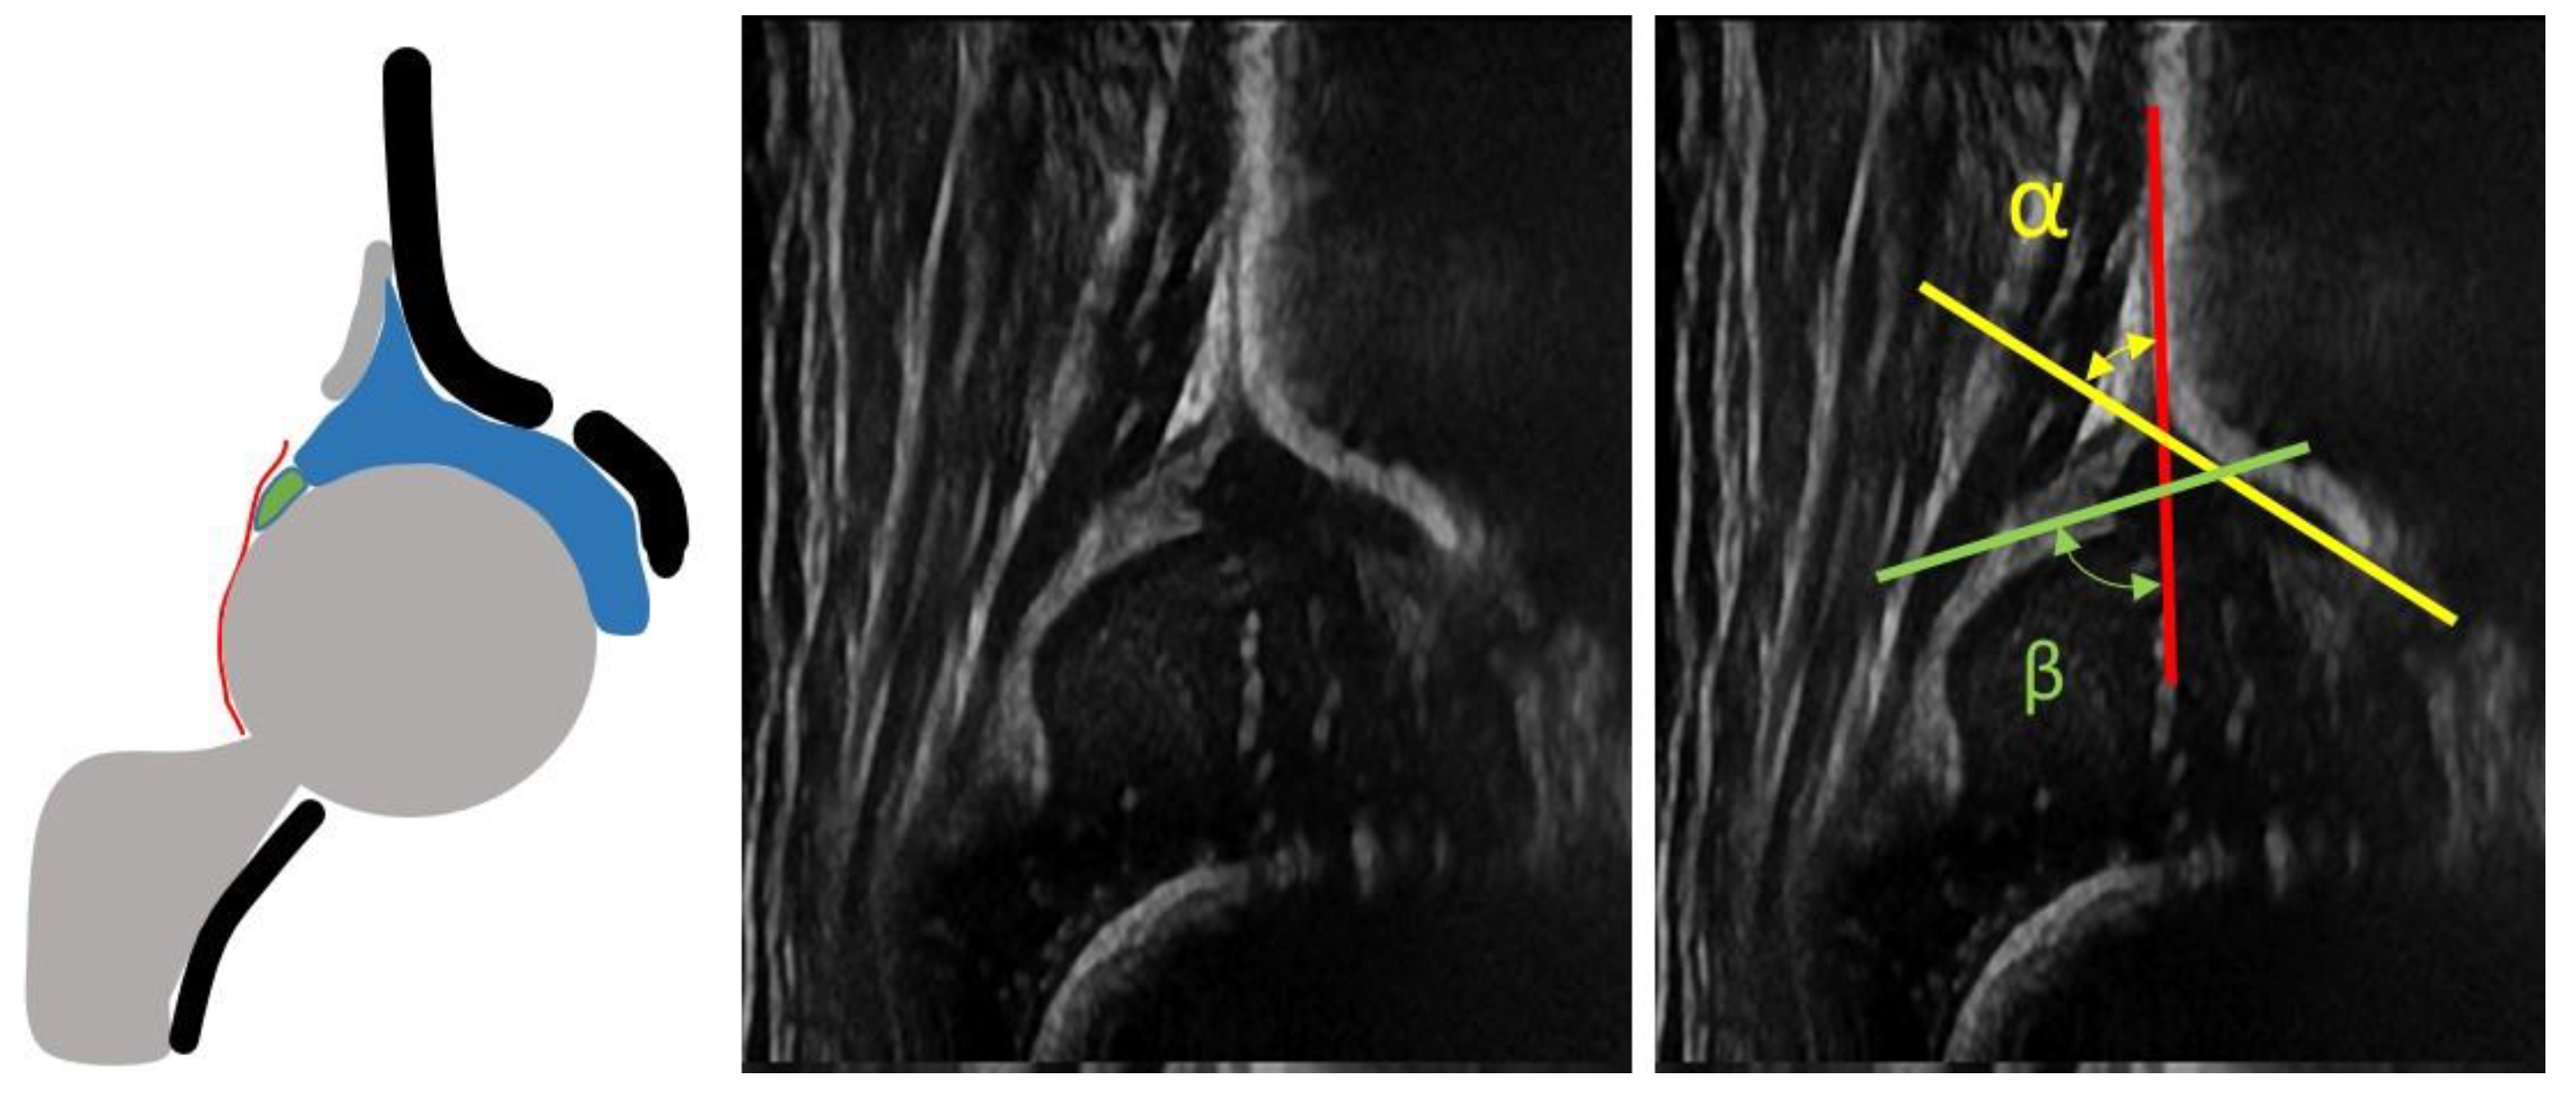

- infants with type I hips at the US examination according to Graf classification (Figure 1)

- infants with non-Type I hips at US examination according to Graf classification